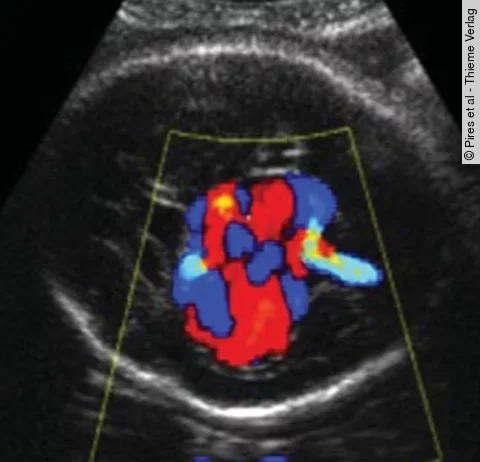

Postpartales BlutungsmanagementWebcast zur Vortragsreihe

Im Namen der British Maternal and Fetal Society fanden an der London School of Hygiene & Tropical Medicine zahlreiche Vorträge zum Thema Management postpartaler Blutungen statt. Gewinnen Sie hier exklusiv Einblicke!